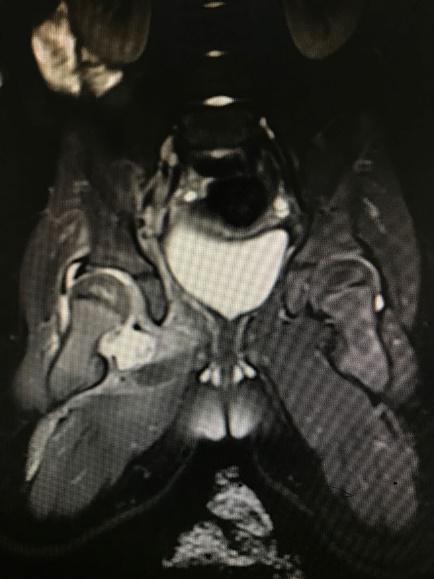

1 资料与方法 1.1 一般资料本研究为回顾性研究,获得医院医学伦理委员会审批(审编号:2020-IRB-035),通过检索本院的电子病例系统,搜索2016年1月1日至2018年12月31日期间出院诊断为“化脓性髋关节炎”的所有病例信息。纳入标准:(1)患儿临床症状、体征、影像学检查、关节液液培养、关节腔液白细胞计数(计数≥50 000 / mm3)、手术或病理证实的化脓性髋关节炎,见图 1~4;(2)关节腔穿刺或手术可见脓性标本。排除标准:(1)年龄>3岁;(2)穿刺或手术未能取得足够标本送检细菌培养者。

| 图 2 MR超示关节腔内积液 |